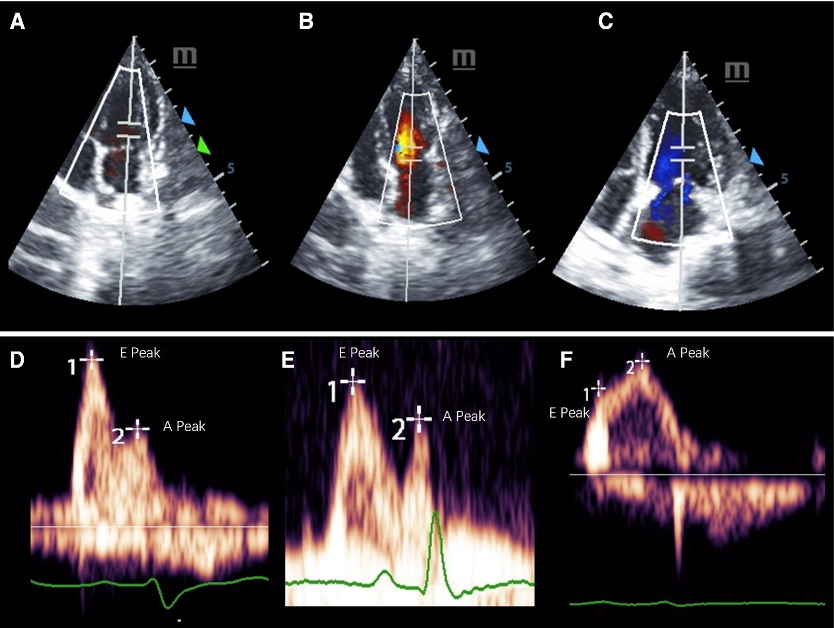

Fig. 1 Representative pulsed-wave Doppler images of mitral inflow in three groups of cynomolgus monkeys. (A–C) shows the measurement location and the (E, F) display the E and A peaks of each group.1

With much experience in the NHP disease model establishment, Creative Biolabs provides the well-established NHP model of HF. Besides, we provide related analysis services including but not limited to echocardiography, Doppler echocardiography, tissue Doppler imaging, histological examination, immunofluorescent staining, real-time PCR analysis, Western Blotting, and microvascular density assessment to assist you in the pathogenesis investigation or therapeutic efficacy evaluation.